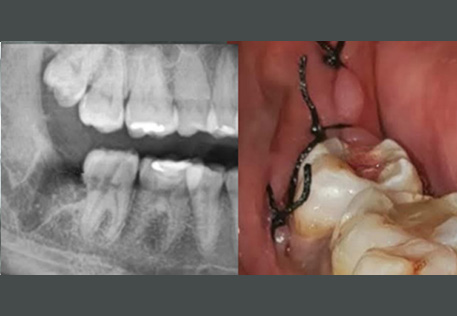

Comprehensive oral examination with digital X-rays to assess the position and condition of your wisdom teeth.

Surgical Extraction: For impacted or partially erupted wisdom teeth, performed with precision by our skilled oral surgeons.

Before / After